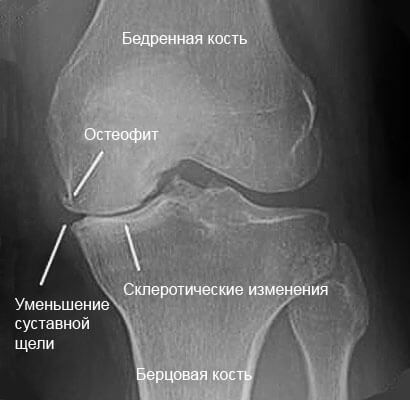

Остеоартроз, как наиболее распространенная форма артрита, проявляется очаговыми повреждениями хрящевой ткани, сужением суставной щели и окостенениями – остеофитами.

Почти 75% людей старше 65 лет имеют признаки артроза коленного сустава: маргинальные (краевые) остеофиты, сужение суставной щели, субхондральный склероз и субхондральные кисты. Причиной обращения к врачу для прохождения рентгена или МРТ является хроническая боль в колене, перенесенная травма. Практически в 90% случаев дегенерация затрагивает медиальную, а также латеральную часть сустава. Маргинальные остеофиты являются важной рентгенографической характеристикой раннего остеоартроза. Сужение суставной щели выявляется гораздо реже, а субхондральные кисты и склероз редко наблюдается у пациентов с дегенерацией суставного хряща.

Помимо остеофитов рентген показывает сужение суставной щели, хондрокальциноз. Разрастание тканей может затронуть латеральный, или медиальный края большеберцовой кости, коленную чашечку, латеральную и медиальную части бедренной кости.

Маленькие наросты растут на костях коленного сустава в горизонтальном направлении, а крупные — по вертикали от линии сустава. Направление роста остеофита и его размер напрямую зависят от сужения суставной щели.